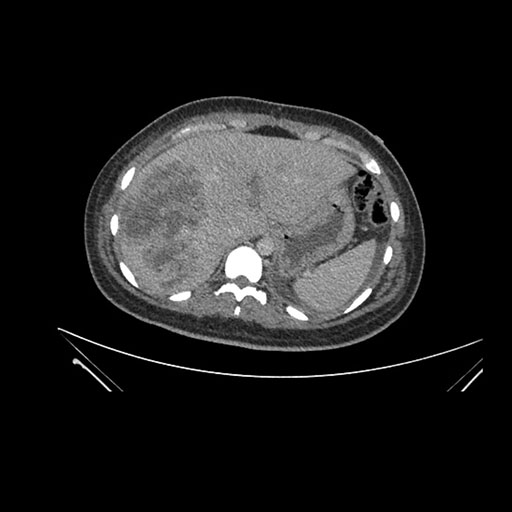

Imaging Analysis

Look through the patient's CT scan to identify any areas of concern for the necessary procedure.

Coronal Arterial

Based on initial findings, which issue(s) would you be most concerned about?